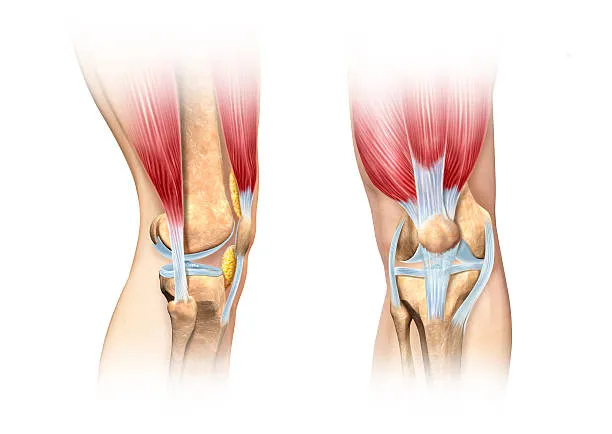

두 번째는 연골 손상

무릎 관절 사이에서 뼈와 뼈의 마찰을 줄여주는 부드러운 조직인 연골이 관련되어 있습니다. 나이 증가, 과체중, 관절염 등으로 인해 연골이 닳거나 소실되면, 뼈 사이의 직접적인 마찰로 인해 통증이 발생할 수 있으며, 이로 인해 움직임의 제한, 삐걱거리는 소리, 염증과 같은 증상이 나타날 수 있습니다.

이 상태의 치료는 체중 감량, 적절한 운동, 보조기 사용과 같은 자가 관리와 필요에 따라 진통제, 항염제, 보호주사, 관절경 수술 등의 의학적 치료를 포함할 수 있습니다.